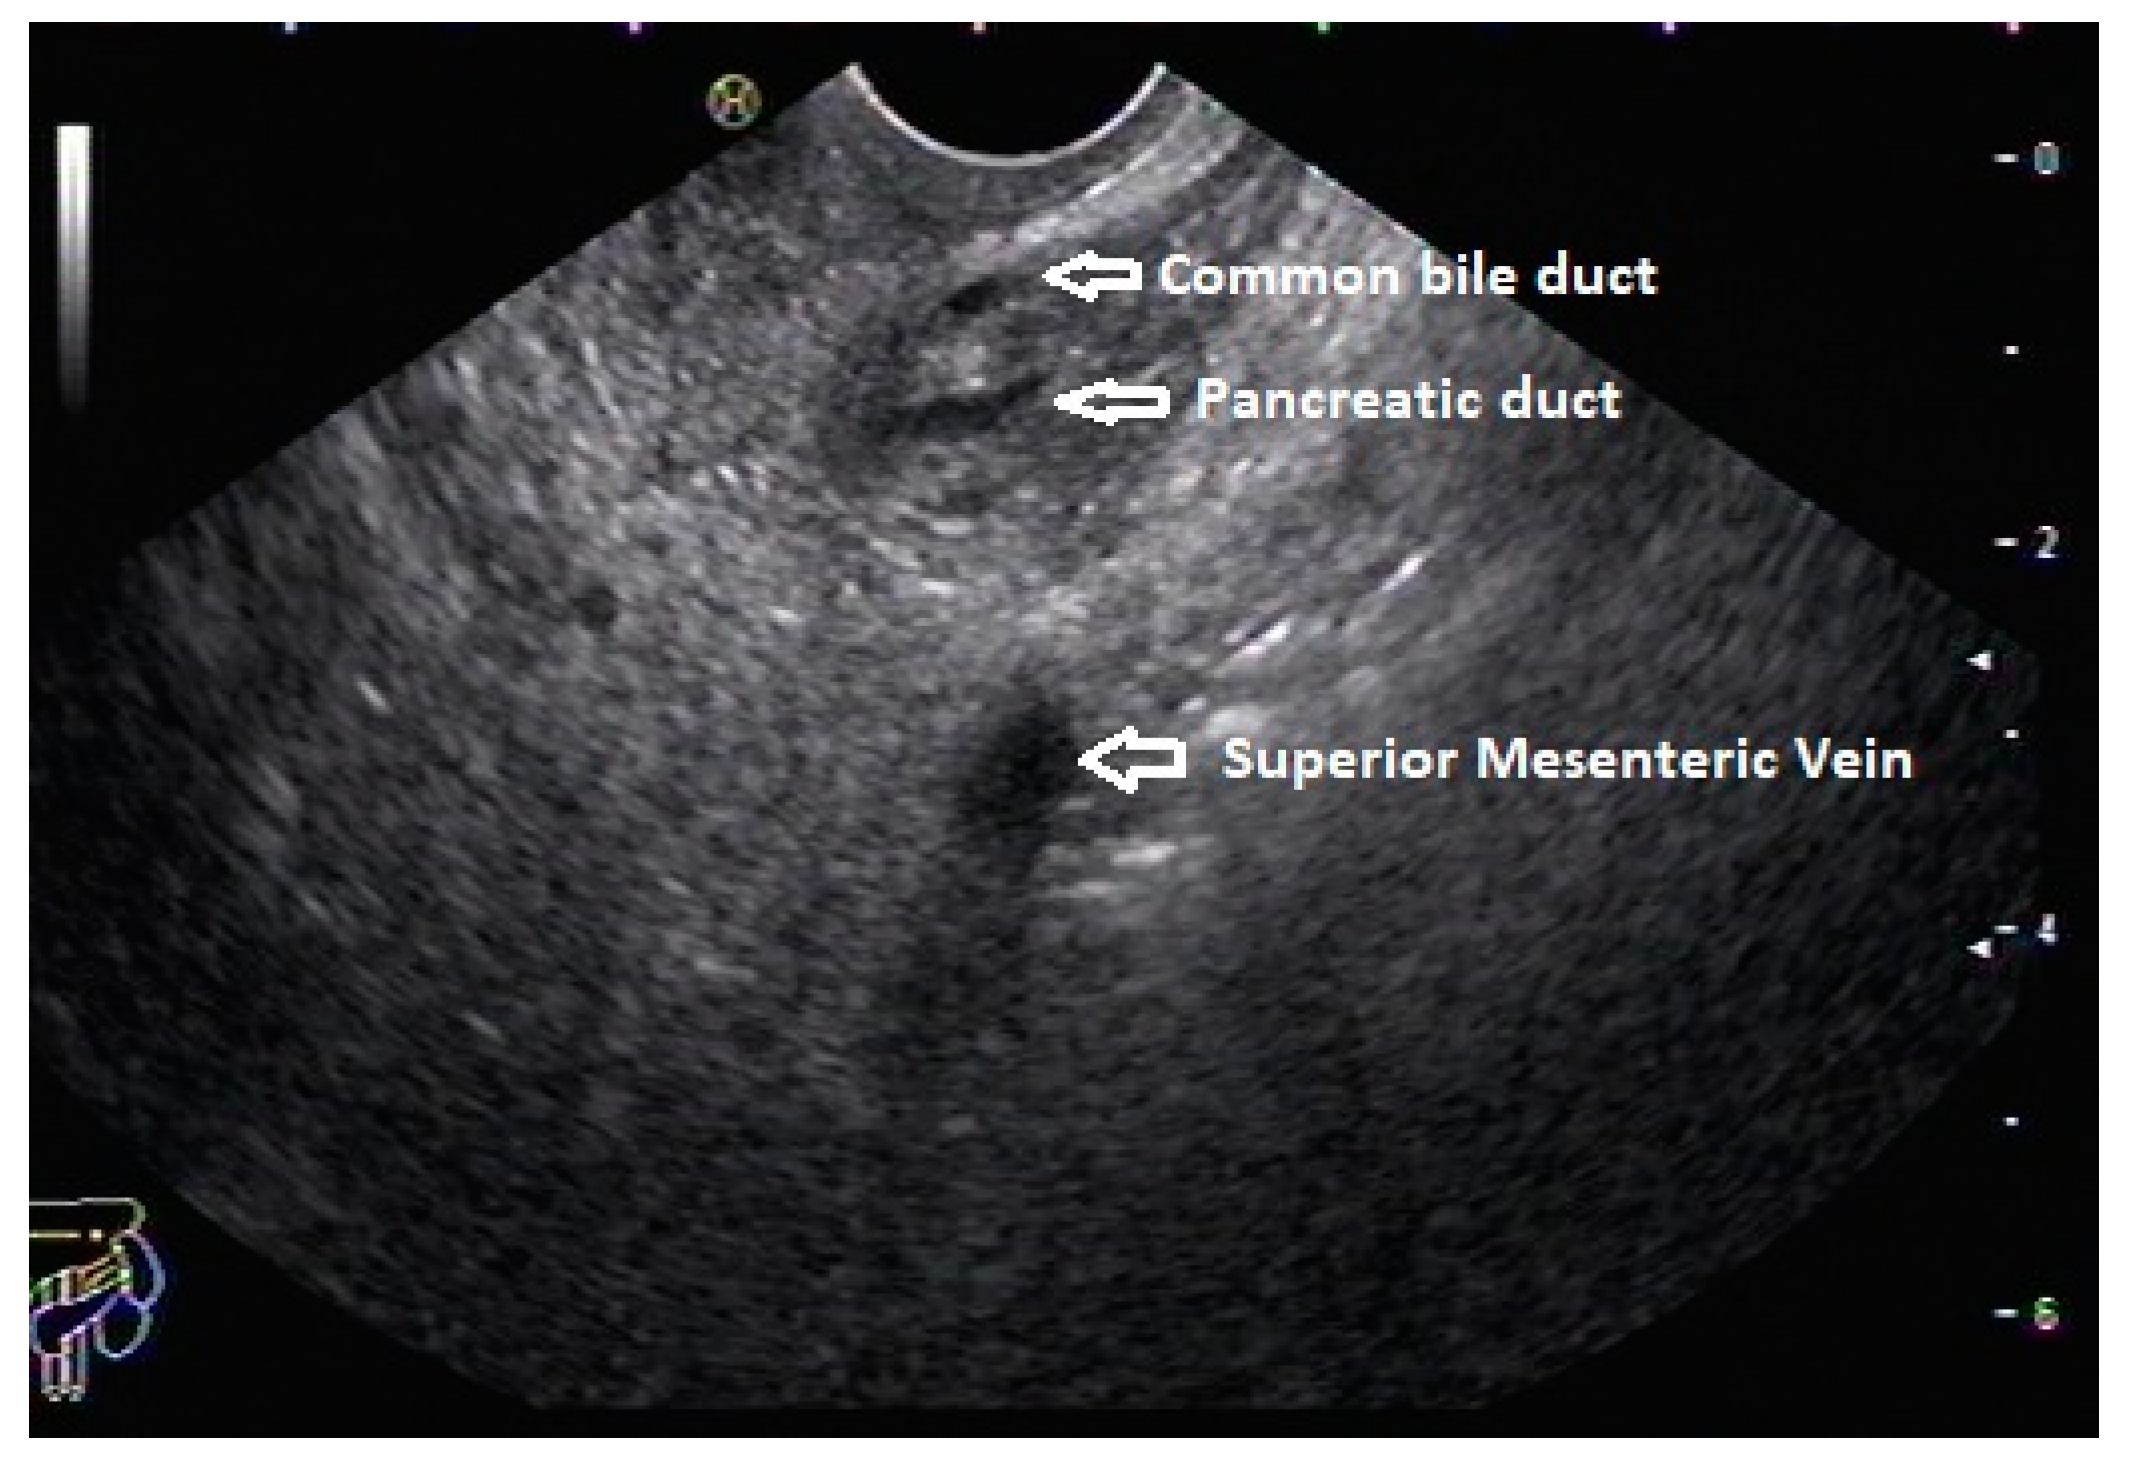

In routine endosonographic examination, all parts of the pancreas are comprehensively examined when seen from three stations, that are the apex of the duodenal bulb, papilla and distal to the papilla. Among these, the best position is the apex of the duodenal bulb as it brings the major portion of the head of pancreas, distal common bile duct and the portal vein in the same frame. For positioning, the EUS scope is advanced along the greater curvature of the stomach and when pylorus is visible, the tip of the scope is negotiated through it followed by air insufflation of the duodenal bulb. This is followed by gentle downward deflection of the tip of the scope making the duodenal bulb visible. Doppler imaging helps differentiating bile duct from the arteries (hepatic artery and the gastroduodenal artery) and portal vein. At this point, the endosonologist gets the view of distal CBD, pancreatic duct, and the portal vein in a single frame in which one structure appears to lie on top of the other and this is called as the ‘stack sign’ (Figure 1) and absence of stack sign suggests possibility of pancreas divisum (Figure 2). As these structures do not lie in the same plane, various manoeuvres like clockwise and counter clockwise rotation and right and left torque are required for a detailed examination of these structures.12 Although this sign is conventionally described in radial EUS, linear EUS can also detect similar anatomical configuration although there are some subtle differences in linear EUS. In linear EUS, usually the ‘stack’ consists of distal CBD and pancreatic duct which are seen on parallel axis (portal vein is not seen). However, superior mesenteric vein (SMV) or artery (SMA) can be seen on linear EUS in a different axis once a clockwise rotation is performed and origin of portal vein from the SMV can also be easily demonstrated (Figure 3).27

Figure 3. Stack sign on Linear EUS.